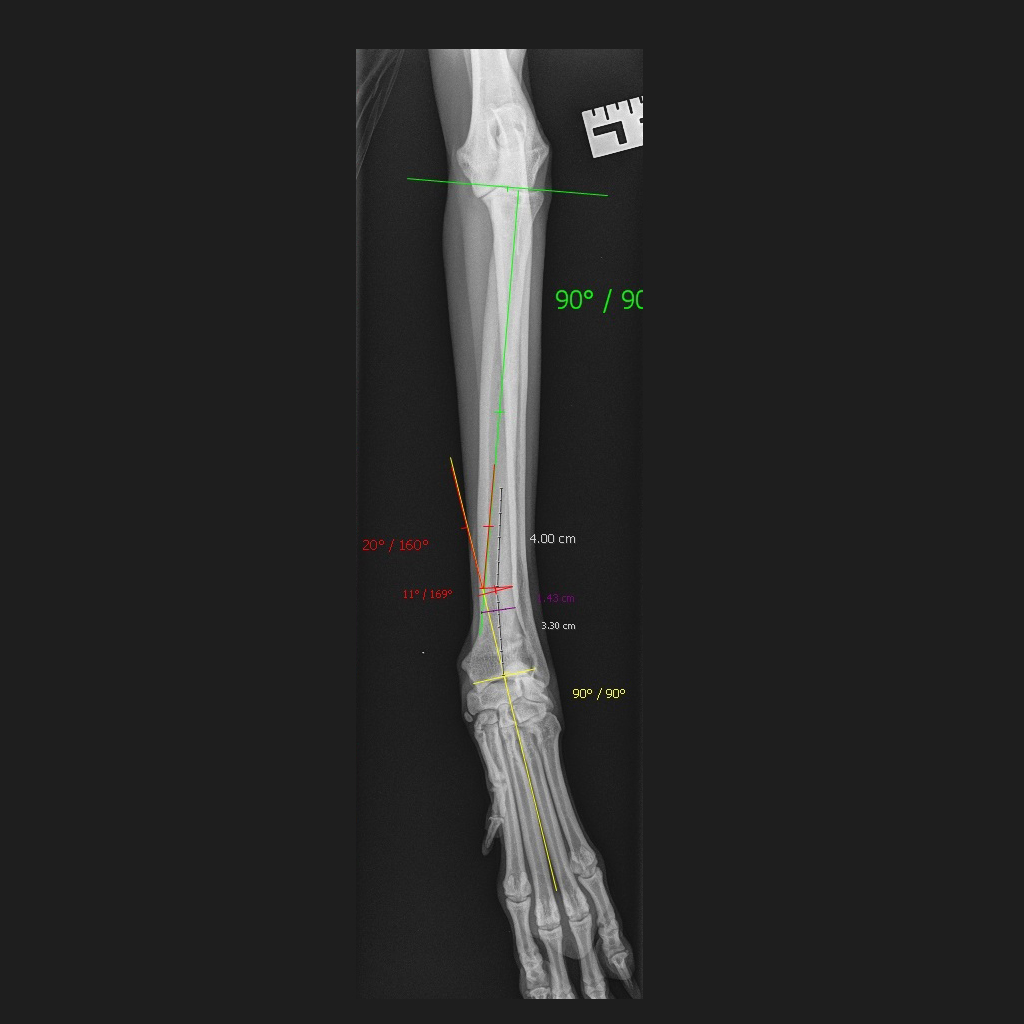

If further investigations are needed, then these typically will take the form of radiographs or CT assessments. These investigations are crucial to fully assess the deformity and to help determine if treatment is required.

In young animals with growth problems, surgery may be aimed at the active growth areas, seeking to adjust the remaining growth of the bone. In older patients, the bone may need to be realigned, and this will be guided by information from the radiographs or CT assessment.

Complicated cases with 3D deformities of the bone may benefit from CT guided surgery using specially designed templates to fit the bone precisely.